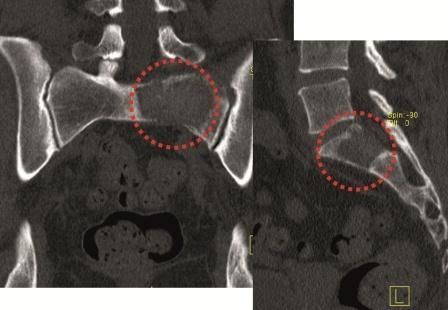

Sakrummetastasen: Stabilitätsgefährdende Metastasen am Sakrum (Abb. 3a) und am hinteren Beckenring werden zumeist mit einer mono- oder bilateralen vertebropelvinen Abstützung versorgt (Abb. 3b). Insbesondere das Os sacrum kann so aus der lasttragenden Kette herausgenommen werden. Vor allem bei Mammakarzinommetastasen kann mit der nachfolgenden Radiatio häufig eine so stabile Rekalzifikation erzielt werden (Abb. 3c), dass mitunter bei Beschwerden über dem Fixateur besonders bei schlanken Patienten eine Metallentfernung erwogen werden kann. Sollte das dorsale Os ileum mit betroffen sein (Abb. 4a) kann bei entsprechenden anatomischen Voraussetzung (Abb. 4b) auch weiter ventral auf den Beckenkamm abgestützt werden (Abb. 4c).